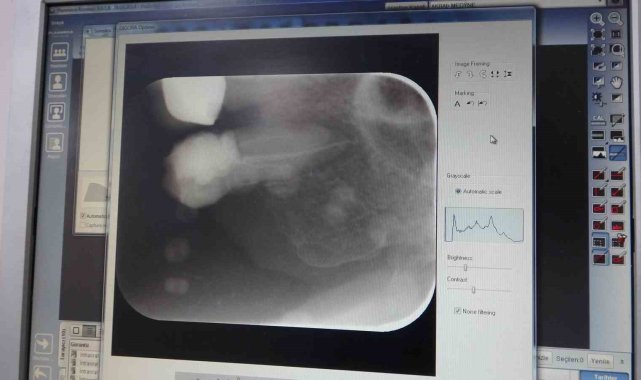

İnönü Üniversitesi Diş Hekimliği Fakültesi'ne 2024 yılında 303 bin hasta başvuru yaparken, yaklaşık 11 bin hastaya kanal tedavisi uygulandı.İnönü Üniversitesi Diş Hekimliği Fakültesi Dekanı ve Endodonti Uzmanı Prof. Dr. Neslihan Şimşek, Diş Hekimliği Fakültesi'ne geçtiğimiz yıl 303 bin hastanın başvuru bulunduğunu belirterek yaklaşık 11 bin hastaya ise kanal tedavisi uygulandığını kaydetti.Tedavi başarı oranının toplumdan topluma değişiklik gösterdiğini kaydeden Endodonti Uzmanı Prof. Dr. Neslihan Şimşek, "Kanal tedavisi öncesi ve sonrasında bir takım görülebilecek akut alevlenme denilen durumlar olabilir. Bu durumu etkileyecek 20'den fazla faktör var aslında. Hastanın yaşı, cinsiyeti, sistemik hastalıklar gibi konular tedavi sürecini etkileyebilir. Yine kadın ve gençlerde daha fazla alevlenmeler ortaya çıkabilir. Bu alevlenmelerin sıklığı ise toplumdan topluma değişebilir" dedi"2024 yılında 303 bin hasta başvuru yaptı"2024 yılında 303 bin hastanın başvuru yaptığını vurgulayan Şimşek, "2024 yılında 303 bin hasta başvuru yaparken, bunlardan yaklaşık 11 bin hastaya kanal tedavisi uygulandı" ifadelerini kullandı. Şimşek, fakültede toplamda 12 milyon 250 binin üzerinde diş tedavisi gerçekleştirildiğini de söyledi.Tedavi ihtiyaçlarının bir çok nedeni olduğunu belirten Dr. Şimşek, "Kanal tedavisinin endikasyonları birden fazladır. Diş çok ağrıdığı zaman veya bir travma ile kırıldığı zaman, protetik işlemler öncesi gibi durumlarda kanal tedavi uygulanabilir. Tedavi sonrasında ise anestezinin etkisi geçene kadar kullanılmamasını ve tedavi uygulanan dişin test edilmemesini tavsiye ediyoruz" diye konuştu.